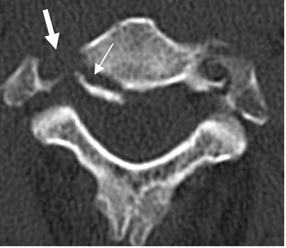

Fig 160. Fractura estable.

TAC axial. Fractura en la parte posterior del cuerpo, que corresponde a la columna media. (Flecha delgada). Igualmente hay fractura de la apófisis transversa, con compromiso del canal de la arteria vertebral. (Flecha gruesa).